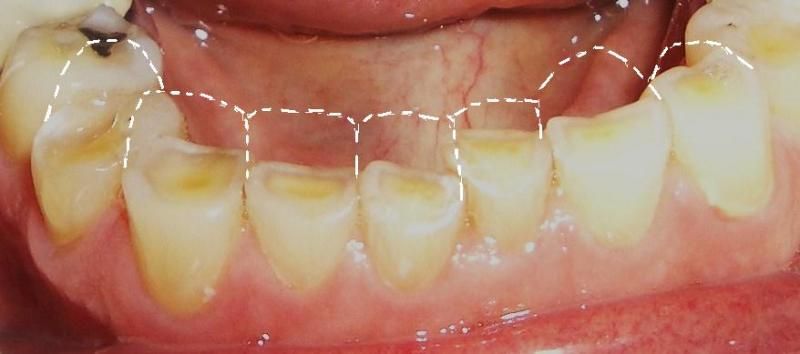

Dấu hiệu nhận biết mòn men răng

Việc phát hiện sớm tình trạng mòn men răng đóng vai trò rất quan trọng, trong việc bảo tồn răng thật. Dưới đây là những dấu hiệu bạn không nên bỏ qua:

2. Thay đổi màu sắc răng

Men răng có màu trắng trong, trong khi ngà răng bên dưới có màu vàng nhạt. Khi men bị bào mòn, răng sẽ dần chuyển sang màu vàng hơn và kém thẩm mỹ. Đây chính là lý do dù vệ sinh răng miệng tốt, nhưng răng vẫn không trắng sáng.

3. Hình dáng răng thay đổi

Mòn men răng lâu ngày có thể làm răng bị biến dạng như:

- Góc cạnh răng bị sứt mẻ, hoặc mỏng đi

- Bề mặt nhai xuất hiện các vết lõm nhỏ

- Răng không đều và dễ vỡ hơn

Dấu Hiệu Mòn Men Răng

Những thay đổi này, không chỉ ảnh hưởng đến thẩm mỹ mà còn làm giảm chức năng ăn nhai.